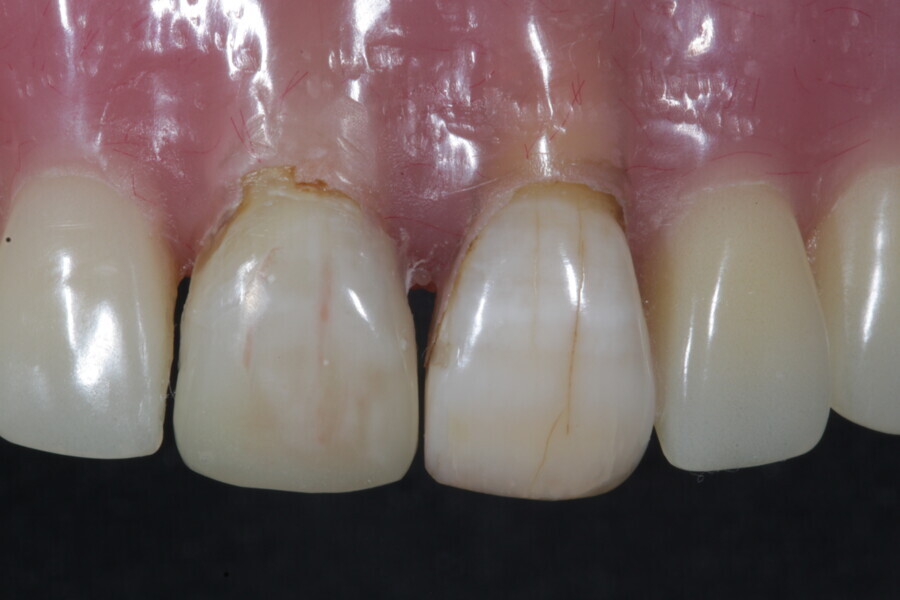

1. functional and aesthetic reconstruction of a maxillary anterior tooth using fibre-reinforced flexible micro-posts after endodontic treatment (Figs. 3–20);

Example 1—showing functional and aesthetic reconstruction of a maxillary anterior tooth using fibre-reinforced flexible micro-posts after endodontic treatment.